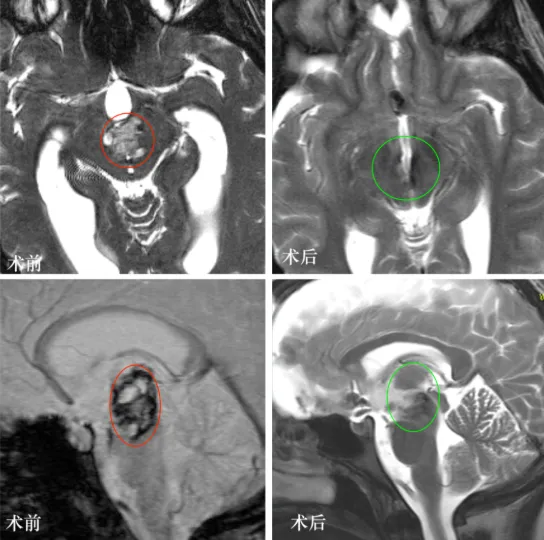

最终,巴教授经前纵裂入路显微镜下成功全切病变,L同学在术后当晚就拔除气管插管,可完全自主呼吸,这一仗,她打赢了!

术后第2天:复查CT正常,病变全切,转至普通病房继续治疗。

术后2年:L同学在享受完美好的大学时光后顺利完成学业,取得本科学位,工作、生活正常如意,复查颅脑MR显示病变全切、无复发,无任何神经功能损伤。